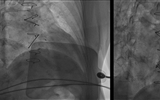

兰大二院心内科完成院内首例经导管二尖瓣“瓣中瓣”植入术